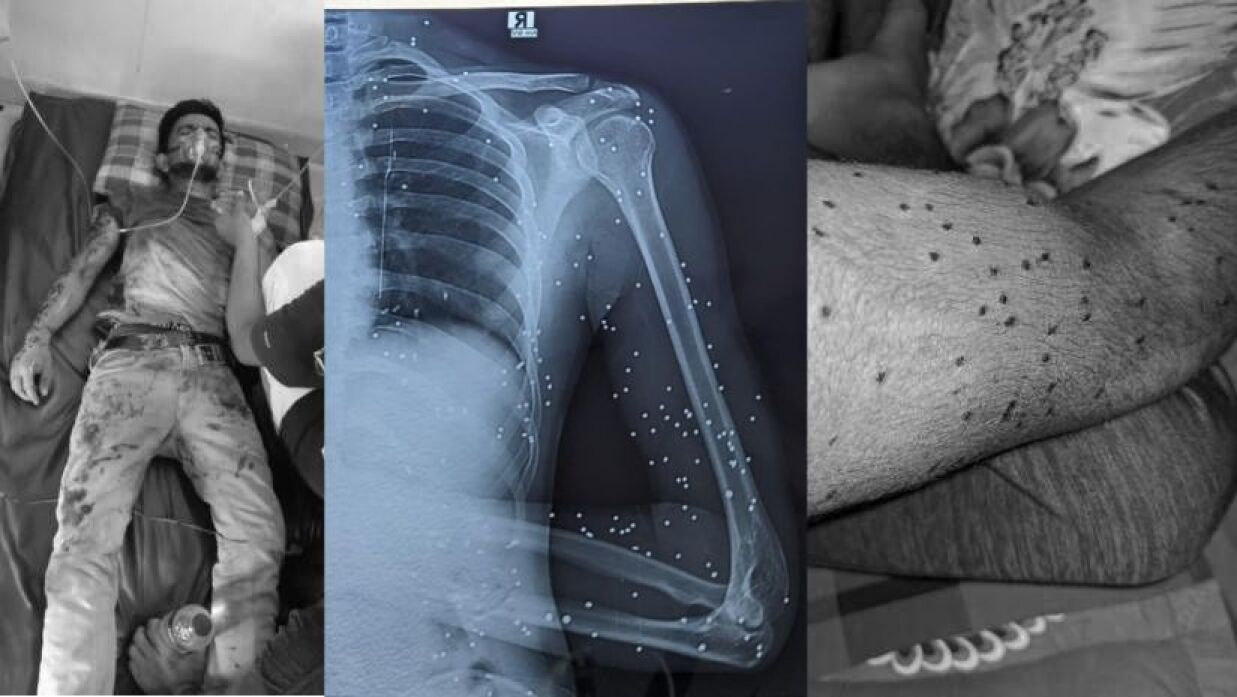

যন্ত্রণায় দিন কাটছে সানজিদুল ইসলামের। শরীরে ২০০ ছররা গুলি। বর্তমানে হাসপাতালের বেডে দুর্বিষহ দিন কাটছে তার। গত জুলাইয়ে বৈষম্যবিরোধী ছাত্র আন্দোলনে যোগ দিয়ে পুলিশের ছররা গুলিতে মারাত্মক আহত হন গাজীপুর মহানগরীর টঙ্গীস্থ তা’মীরুল মিল্লাত কামিল মাদ্রাসার শিক্ষার্থী সানজিদুল ইসলাম।

বর্তমানে ঢাকার সম্মিলিত সামরিক হাসপাতাল (সিএমএইচ) চিকিৎসা নিলেও জুলাই ফাউন্ডেশন থেকে পাননি কোনো ধরনের সহায়তা পাননি। এমনকি আহতদের তালিকায়ও তার নাম নেই, কোনো ক্যাটাগরিতেই অন্তর্ভুক্ত করা হয়নি। বৈষম্যের বিরুদ্ধে লড়াই করতে গিয়ে নিজেই হলেন বৈষম্যের শিকার?

জানা যায়, দুপুর দেড়টার দিকে গুলিবিদ্ধ হন তিনি। পরে তার সহযোদ্ধারা তাকে দ্রুত উত্তরা কুয়েত মৈত্রী হাসপাতালে নিয়ে যান। কিন্তু সেখান থেকে জানিয়ে দেওয়া হয়, এক্সরে করা সম্ভব নয়। এক বন্ধুর ভাইয়ের সহযোগিতায় সেদিন মেসে ফিরে যান তিনি। পরদিন গুটিয়া ইন্টারন্যাশনাল হাসপাতালে এক্সরে করান।

এখনও শরীরে ২০০-র বেশি ছররা গুলি নিয়ে দিন পার করছেন সানজিদুল। প্রচণ্ড ব্যথা, দুর্বলতা নিত্যসঙ্গী।